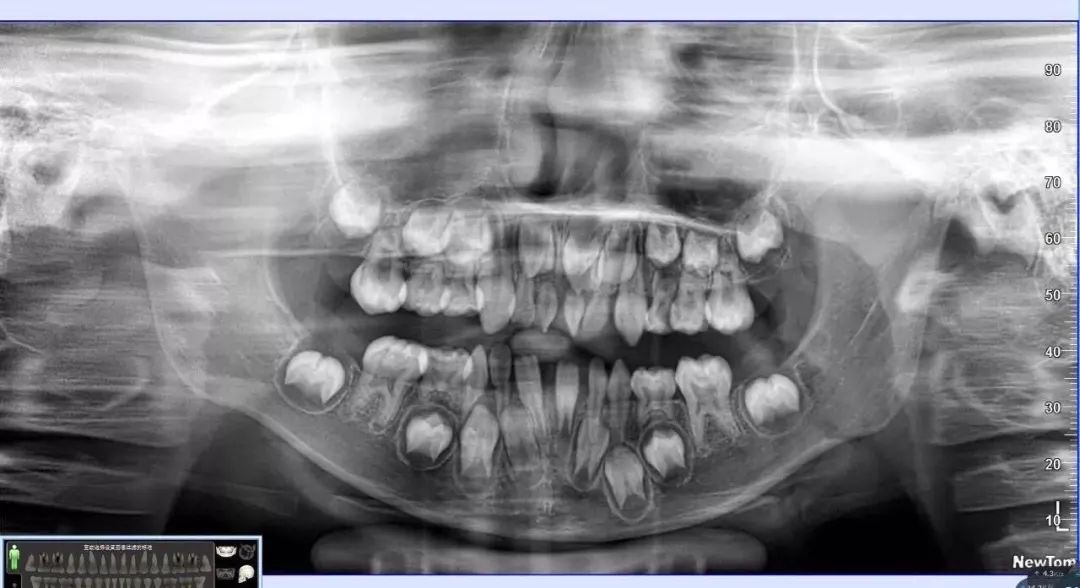

(1) 全景曲断片

全景曲断片

以检查全口牙齿为目的,全景曲断片可以观察到全口牙的形态、位置、颌骨等情况,比如乳牙下方是否有恒牙牙胚在发育、牙颌的畸形程度等等。